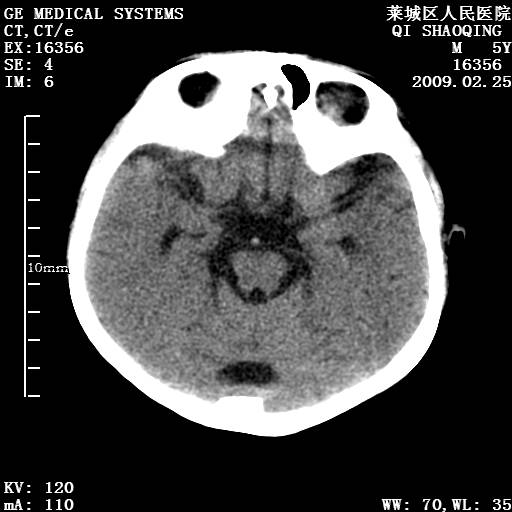

以下是引用wangzhengyuan在2009-2-28 10:22:00的发言:[br]甲状旁腺功能减退引起的脑改变.

以下是引用zsl6918在2009-2-28 10:17:00的发言:[br]首先考虑甲状旁腺功能低下所致,可结合实验室检查明确.另外需除外先天性宫内感染所致.

以下是引用余辉在2009-3-1 9:35:00的发言:[br]患者明显的肢体及智力改变,不支持fahr病,多考虑甲旁低,有可能伴有甲低(呆小症).进一步检查。